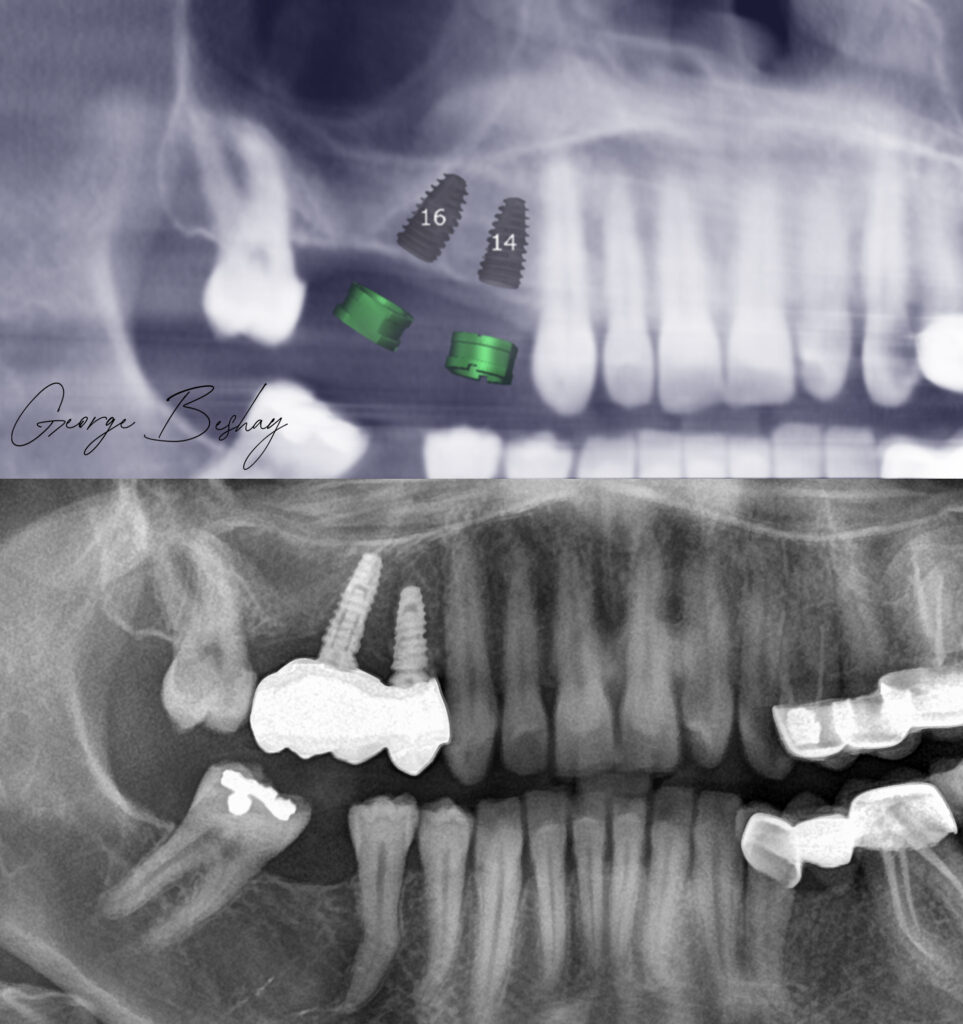

The patient needed posterior maxillary rehabilitation.

Limited vertical bone height.

Sinus floor close.

The conventional route?

Sinus lifting.

But when we planned the final prosthesis first — the occlusion, load direction, and restorative design — we realized we could approach it differently.

We placed a tilted implant, engaging available native bone, and restored the case with angled MUAs and a carefully planned distal cantilever to restore the molar.

No sinus lift.